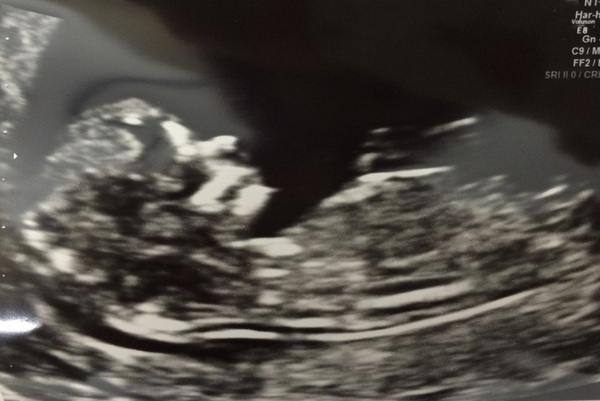

I had my scan on Wednesday and all went well, yay. My first reaction was oh good there is something in there. Phew. Not imagining it. Here's the pic. Oh and due date one day forward to November 15th. My mum's already knitted a lovely blanket (she's a star knitter - so glad it's a winter baby, she can go crazy with the wool!)

Great pic helo! Strong nose!